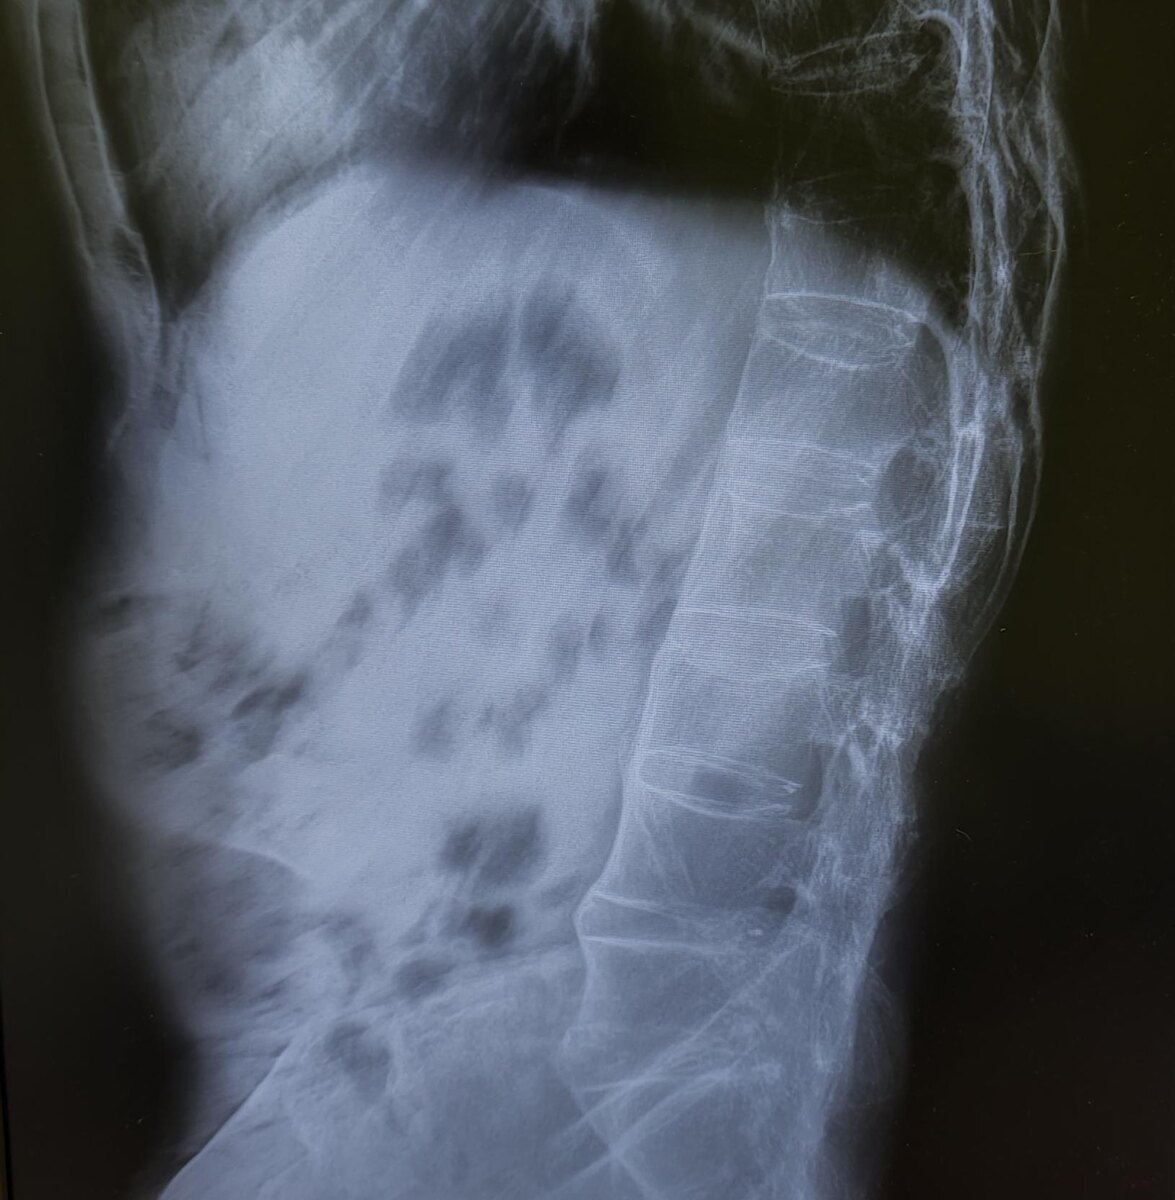

На Р-граммах поясничного отдела позвоночника в 2х проекциях: структура костной ткани позвонков разряжена, высота тел L3,L5 неравномерно снижена в пределах 20% в передних и средних отделах, неравномерное умеренное сужение межпозвонковых рентгенологических пространств, субхондральный склероз замыкательных пластинок, краевые остеофиты. Оссификация передней продольной связки позвоночника на всем протяжении-синдесмофиты.

Заключение: Анкилозирующий спондилит поясничного отдела позвоночника (б.Бехтерева).Дегенеративно-дистрофические изменения поясничного отдела позвоночника. Остеопороз.